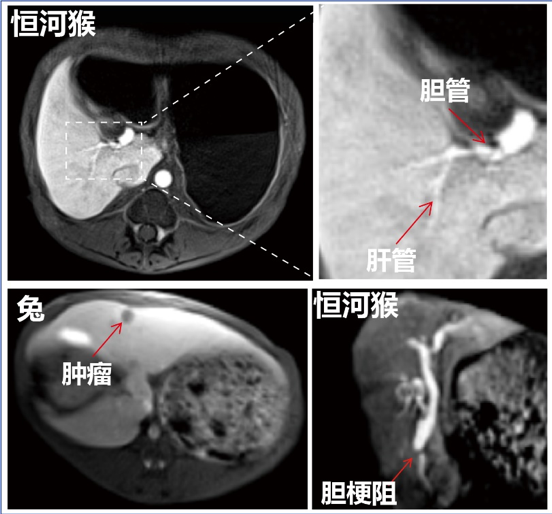

为获得大量、可靠的实验数据,樊海明与四川大学华西第二医院和中山大学附属第三医院合作,利用其磁共振成像设备开展大动物科学实验,数据表明,“玵立显®”可高特异性的靶向正常肝细胞,从而实现了早期肝癌微小病灶的精准影像检出;其肝对比度较临床特异性对比剂提高了5.8倍,可清晰分辨0.5毫米的肝管;肝胆期显影也从15分钟缩短到5分钟,显著提高了影像检查效率。更值得一提的是,“玵立显®”还能够通过肝胆代谢系统快速排泄,大幅减少了体内残留纳米颗粒带来的潜在副作用。

“‘玵立显®’通过静脉注射进入人体后会抵达肝脏,其表面的两个靶头像两只手握手一样与正常的肝细胞紧密结合在一起,从而在磁共振成像上‘点亮’整个肝脏,同时因为它不与肿瘤细胞结合,导致肿瘤在图像上显示为暗点。它就像一个探照灯一样,帮助人们以可视化的方式发现病灶。”樊海明介绍。

我国肝癌的发病人数非常高,而五年总体生存率仅有 14.1%,主要原因是肝癌发病比较隐匿,当大多数患者确诊时,往往已经处于中晚期。“现有的对比剂仅能诊断识别1厘米以上的病灶,而‘玵立显®’可以高效识别0.5厘米,甚至更小的病灶。” 樊海明介绍。“能否在更早期发现病灶,是肝癌患者救治的生死分界线”。